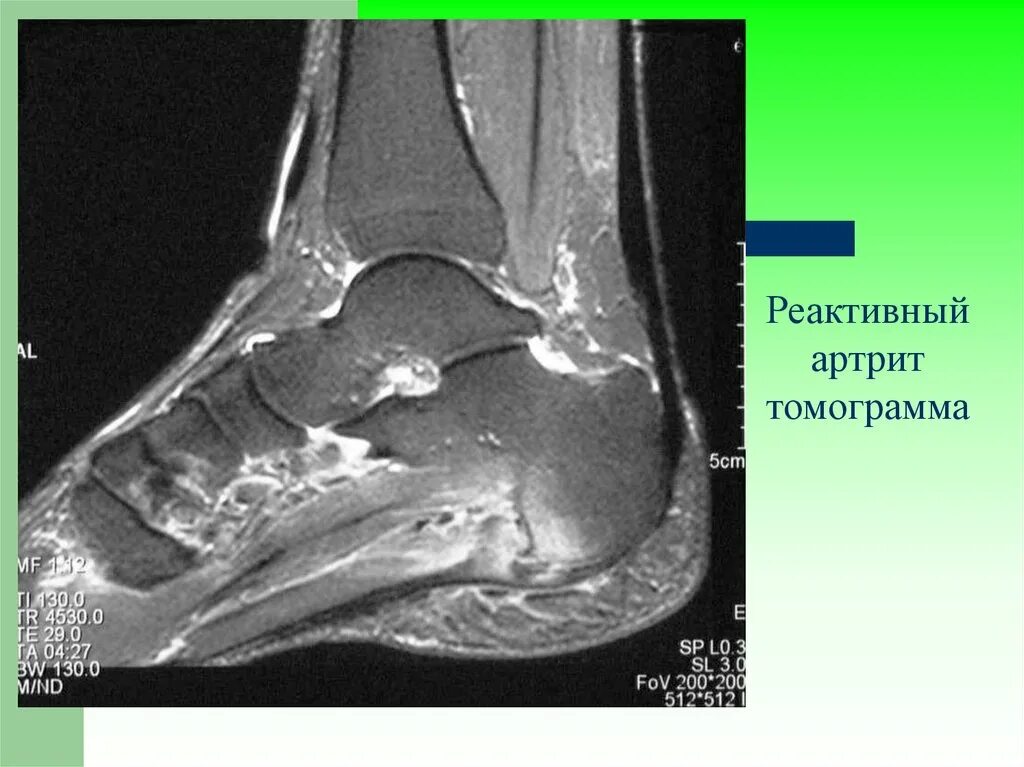

Артроз пяточных суставов